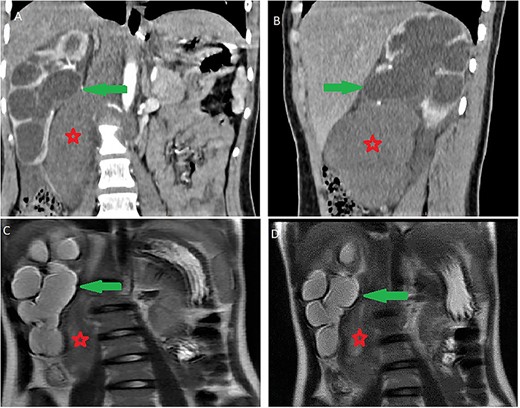

Microscopic scrutiny of the resected specimen; the observed ganglion cells (red arrow) are mature, having a compact, eosinophilic cytoplasm and a single eccentric nucleus with prominent nucleolus; Schwann cells (black arrow) are also mature—HE;400X.

Histologically, it is characterized by large ganglions cells proliferation with eosinophilic cytoplasm, large clear nucleolus without atypia, in a loose fibrillar background. This was the case of our patient; no immature neuroblastic component was noted. Histological study of the surgical specimen is essential, to eliminate a contingent of neuroblastoma and pheochromocytoma within the GN, which can be missing on a core biopsy [10].